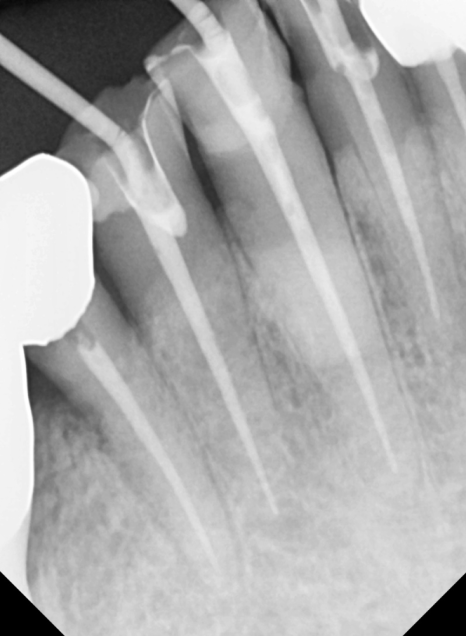

240502

보철물을 올릴 때는

음식물이 최대한 끼지 않도록

정밀하게 설계하는 데 집중했습니다.

크라운 세팅 시에는 치간 칫솔 사용법을

상세히 설명해 드리며

관리 방법도 잊지 않고 안내해 드렸어요~

240711

치료가 마무리된 후의 모습입니다.

검게 변색되었던 부분들이 사라지고

인상이 전체적으로 깨끗하고 단정해 보이네요.^^

240223(전) 240711(후)